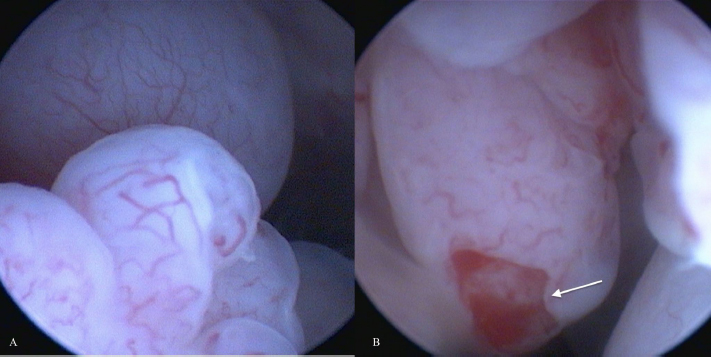

An obstructive urethral mass did not allow endoscopic examination of the urinary bladder in one case (number 6). Both dogs with indirect signs of ureteral occlusion showed bilateral ureteral papillae involvement at endoscopic examination. Four of six endoscopically evaluable tumors appeared as grape-like shaped masses (Fig. 1) and two as solid, and sessile masses. Both latter were located dorsally on the bladder body. The grape-like shape was associated with a friable consistency, while solid and sessile masses resulted in firmness. The cytological examination was performed in six cases but failed to diagnose RMS in four cases. In two cases an atypical spindle cell population was observed, suggesting mesenchymal origin. Histological diagnosis of RMS was reported in five of seven cases. Two cases were classified as round cell tumors and not further classified as spindle cell tumors at morphological examination and as RMS after immunohistochemistry (desmin +). Mitotic count was reported in six of seven cases and resulted low in two cases and a high in four (Table 2).

Fig. 1. (A and B): Endoscopic appearance of canine ubRMSs: grape-like shaped vascularized masses with pale pink color and friable consistency. The arrow indicates tumor ulceration.